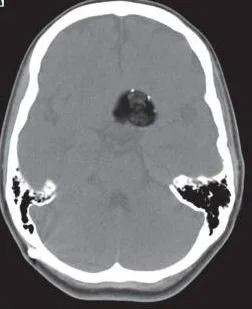

Our patient had a ruptured dermoid cyst with a lipid/fluid interface in the ventricle.  Dermoid cysts are present at birth and occur when ectoderm  layers don’t grow together normally. They contain remnants of ectodermal tissue including sebaceous cysts, oil producing  hair follicles, squamous epithelium and sometimes teeth.  They most commonly present in the first three decades of life. Dermoids are the most common pediatric tumor and are found in the orbit and periorbital areas often over the L eyebrow.

the lipid/csf interface from a ruptured dermoic

In the brain dermoids account for <1% of all intracranial masses They are most commonly found in the midline because they are felt to be ectopic ectoderm from the neural tube. They are often in the suprasellar cistern.  As they grow they are at risk for rupture and serious complications such as chemical meningitis, vasospasm and infarct can occur.

Our patient is still hospitalized.  He had a ventricular drains placed for progressive hydrocephalus, aseptic meningitis was diagnosed, and hyponatremia developed.   This was treated with tolvaptan.  He is awake and alert with slight expressive aphasia with drains still in place.